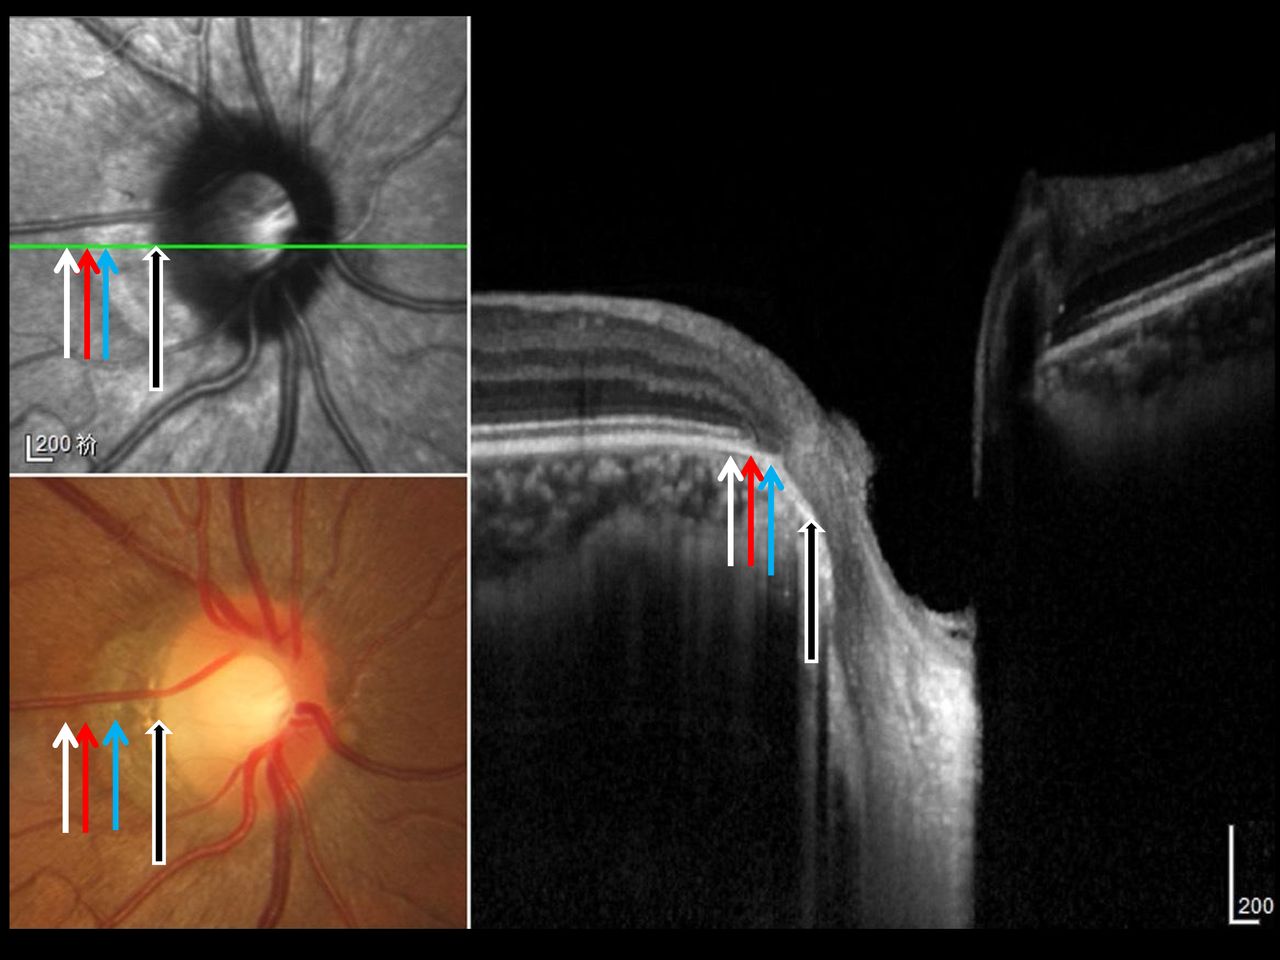

이부분을 광학 단층촬영으로 유심히 관찰하면, Bruch membrane 이라는 브루크막이 있는 부분이 있고 없는 부분이 있습니다.

Beta zone PPA 중에서 Bruch membrane 이 있는 곳을 새롭게 Beta zone 이라고 정의하고 있고,

Beta zone PPA중에서 Bruch membrane 이 없는 곳을 Gamma zone이라고 명명하고 있습니다.

그럼 Alpha zone 이 가장 바깥쪽에 위치하고 그 안쪽에 Beta zone , 가장 안쪽에 Gamam zone 이 위치하는 형태가 됩니다.